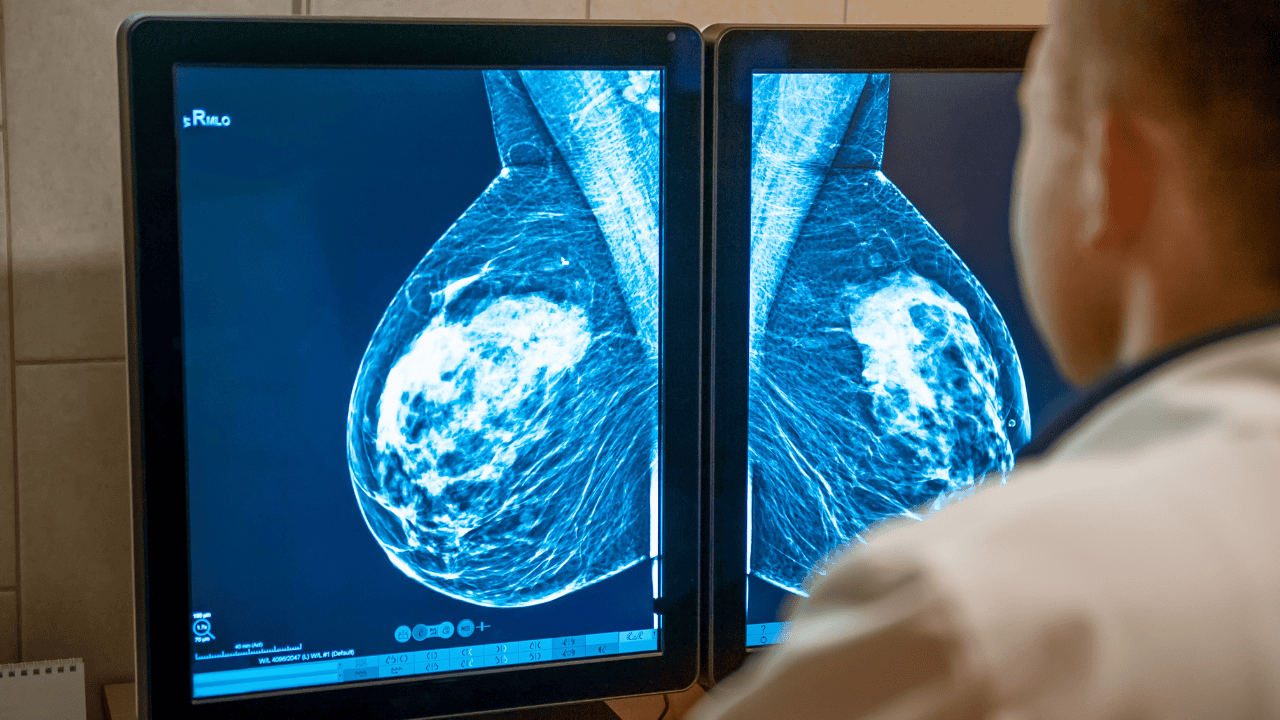

Bezpłatne badanie mammograficzne w ramach akcji to zorganizowane, finansowane publicznie zaproszenia do wykonania przesiewowego zdjęcia piersi w określonej grupie wiekowej. Ponad 1,5 mln kobiet otrzyma imienne zaproszenie na bezpłatną mammografię, co zwiększa szanse na wczesne wykrycie zmian.

Bezpłatne badanie mammograficzne w programie przesiewowym jest adresowane do kobiet o podwyższonym ryzyku związanym z wiekiem. Skuteczność tak zorganizowanej profilaktyki wynika z wczesnego wychwytywania zmian, zanim pojawią się dolegliwości. Rak piersi jest najczęściej diagnozowanym nowotworem złośliwym u kobiet w Polsce, dlatego regularne wykonywanie badań przesiewowych realnie zmniejsza odsetek późnych rozpoznań. Przeczytaj: Mammografia to czasem za mało. U kobiet z gęstymi piersiami lepiej sprawdzają się inne badania